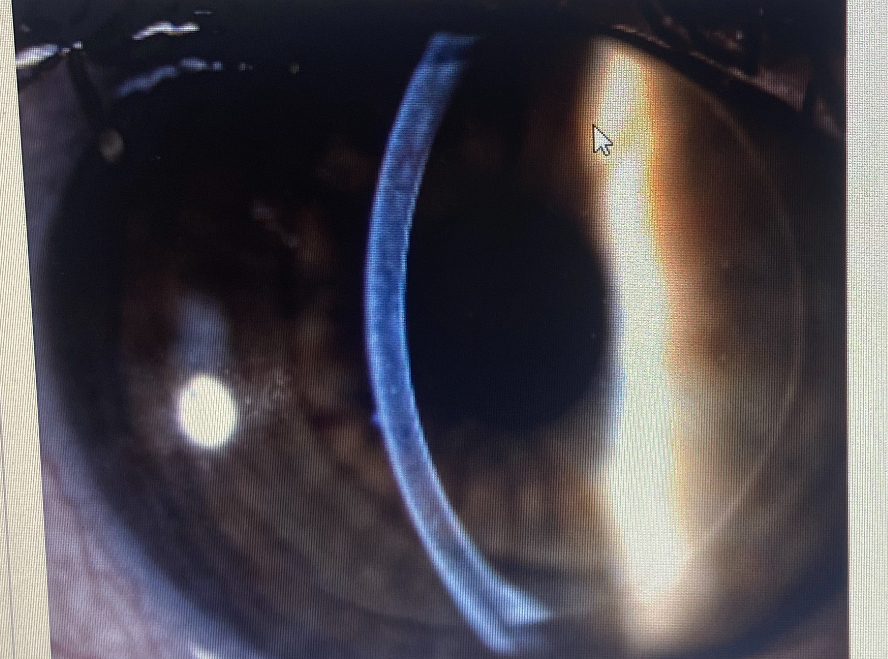

What slit lamp technique is this

Optic section

what slit lamp technique is being demonstrated in the image

what slit lamp technique is being demonstrated on the model eye in this image